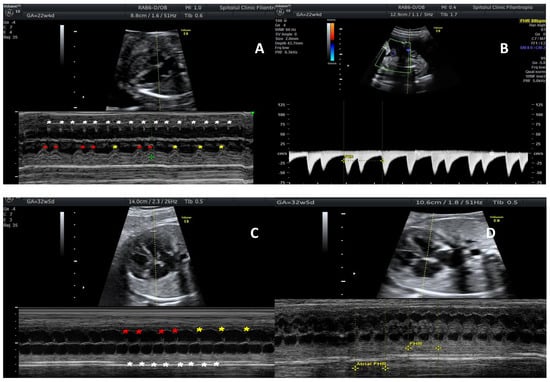

2. Case Report